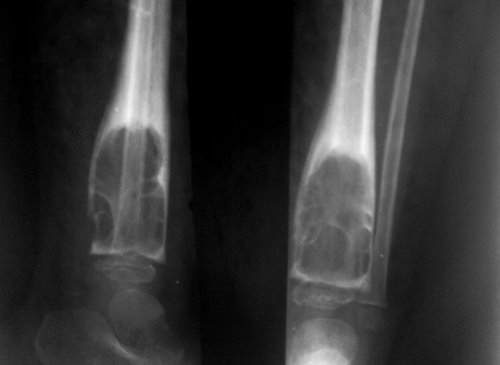

Диагностирование

Диагностирование патологического процесса основано на физикальном осмотре пациента, сбора анамнестических данных. В дополнение показано рентгенологическое исследование костного аппарата. В качестве дополнительных исследований применяют: